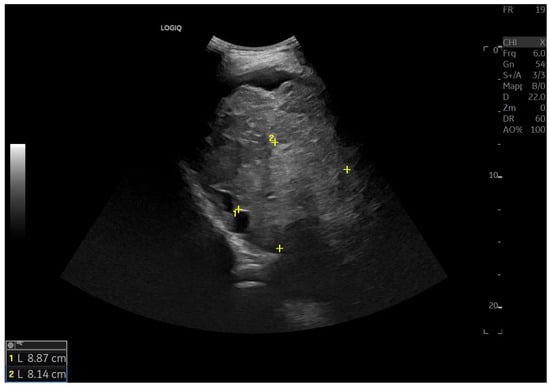

Figure 6.

Diffuse echostructural change of the left lobe with a heterogeneous hyperechoic area measuring 89 × 81 mm.